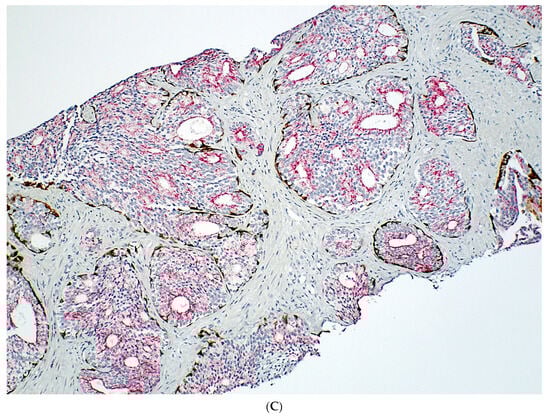

Although exceedingly rare, IDC-P has been observed in association with only GG1 PCa, distant from high-grade PCa, or even without a concurrent PCa (Figure 1) in rare RP specimens; and in these scenarios, IDC-P may represent a precursor lesion in prostate carcinogenesis rather than retrograde spread of high-grade PCa into pre-existing ducts and acini (see discussion below). IDC-P identified in these contexts have been reported in literature by various institutions [18,22,23,24,25,26,27,28], though some of these reports are not as convincing due to partial submission of RP specimens. A summary of the reported cases is provided in Supplementary Table S2.

Figure 1.

Isolated IDC-P without concomitant prostate cancer in a prostate biopsy (A,B). The IDC-P glands have residual basal cells positive for basal cell markers (brown stains) and are also positive for AMACR (red stain) (C). Isolated IDC-P is associated with unsampled GG ≥ 2 PCa in the majority of cases, although no invasive or only GG1 PCa is found in subsequent RPs in approximately 10% of cases.